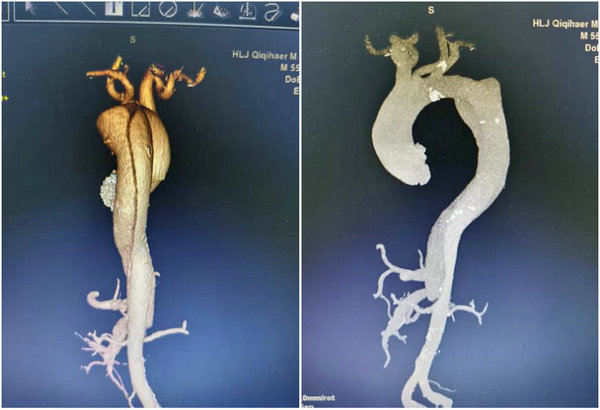

55岁的李先生,因右手痛风石就诊于齐医附属二院骨外科住院治疗,在院期间患者突然一股疼痛感从胸部及背部袭来,令他疼痛难忍,休息后仍不能缓解,骨外科医生立即邀请血管外科进行会诊,经过血管外科王颖主任的一系列专科查体及询问病史初步诊断为主动脉夹层,必须转科手术治疗。医院立刻为李先生开通绿色通道,对他进行血压监测及主动脉CTA检查,结果提示:李先生为B型主动脉夹层动脉瘤且高血压三级,血管撕裂严重,随时可能会出现动脉破裂、急性循环衰竭或猝死等生命危险。

患者术前CTA检查提示

支架植入前(左)与植入后对比